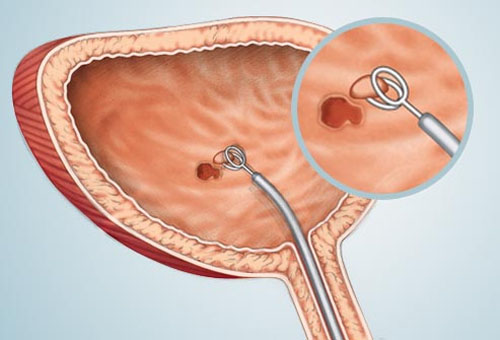

Nếu bạn có nguy cơ cao bị ung thư bàng quang hoặc có nhiều triệu chứng khả nghi bệnh như trê, các bác sĩ sẽ yêu cầu bạn làm xét nghiệm nước tiểu. Nếu cần thiết, bác sĩ sẽ tiến hàng nội soi bàng quang để thấy cụ thể bên trong bàng quang. Kiểm tra sinh thiết là cách tốt nhất để chẩn đoán ung thư và nó được thực hiện khi các biện pháp trên không cho kết quả rõ ràng.

Nội soi để thấy được những bất thường bên trong bàng quang

- Phẫu thuật cắt bỏ: Phương pháp cắt bỏ u qua nội soi được áp dụng với những ung thư ở giai đoạn sớm (u còn ở bề mặt). Bác sĩ đưa một ống soi vào bàng quang qua niệu đạo, sau đó sử dụng một dụng cụ có dạng sợi thòng lọng nhỏ để lấy bỏ khối u và đốt những ung thư còn lại bằng dòng điện.